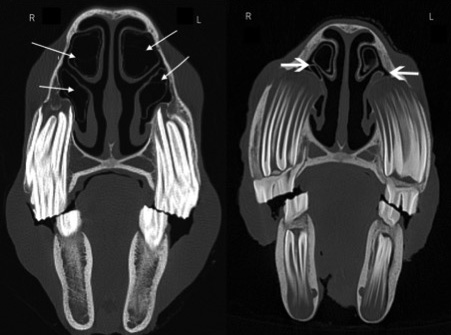

An anatomical study of the dorsal and ventral nasal conchal bullae in normal horses: Computed tomographic anatomical and morphometric findings

Involvement of dorsal and ventral nasal conchal bullae can be clinically important in sinusitis. This study aimed to describe the computed tomographic anatomy of these structures: 90 equine heads were obtained from abattoirs and their age estimated from dentition. Computed tomography images were acquired and examined by diplomats. Specimens with dental or sinonasal disease (confirmed by skull sectioning and gross examination) were excluded from the study, leaving 60 specimens.

Imaging software (OsiriX) was used to create multi-dimensional reconstructions  and measure height, length and width of dorsal and ventral bullae allowing the volume of each bulla to be calculated. Height, length and width of each head also provided a volume for each skull.

The dorsal conchal bullae were found to be greater in volume (average 24 cm3) than ventral conchal bullae (average 15cm3) and these were related to head size. In both dorsal and ventral bullae, there were significant differences in the volumes between different age groups, with those in the youngest group (0–5 years) having significantly smaller volumes than those in the oldest group (over 16 years). In the case of the ventral conchal bullae, this could be explained by the larger size of cheek teeth alveoli protruding into the nasal cavity in younger horses.

In the majority of horses (81.3%) the rostral limit of the dorsal conchal bulla was parallel to Triadan 07s. The caudal limit was parallel to Triadan 10s in 61% and the 09s in 30.5%. The rostral limit of the ventral conchal bulla was parallel to Triadan 07s in 78% and the caudal limit parallel to the 09s in 64.5% and the 10s in 32%. This shows that in some horses the caudal limits of the ventral conchal bulla can overlap with the rostral extent of the rostral maxillary sinus.